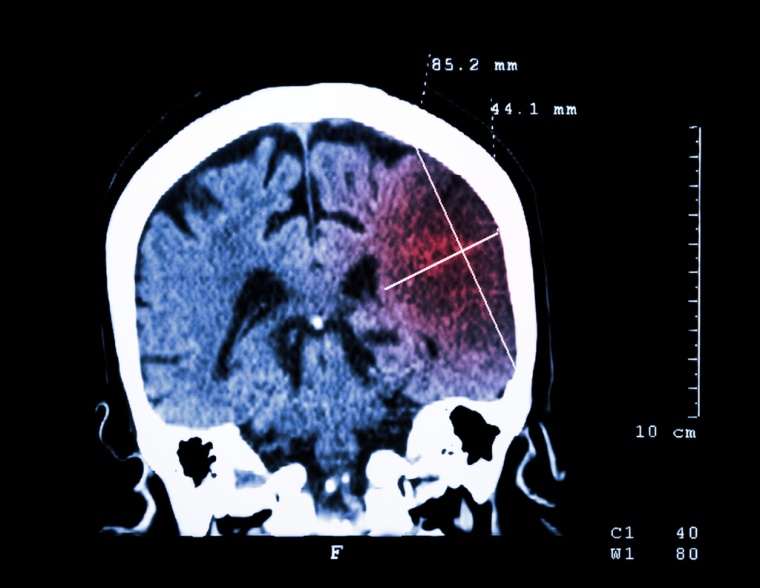

Wie der Experte ausführt, kann es gerade in Ballungsgebieten, wo sich der Verkehr staut, aber auch in ländlichen Regionen, wo der Weg in die nächste Stroke Unit weit ist, zu Verzögerungen kommen, bis der Rettungswagen mit dem Patienten die Klinik erreicht. Genau hier setzt ein Berliner Projekt an: Derzeit sind in der Hauptstadt STroke Einsatz-MObile (STEMO) im Einsatz, speziell konzipierte Rettungswagen, die mit einem Computertomographen und einem Minilabor ausgerüstet sind. Vorteil: Die therapierelevante Untersuchung des Patienten mit Bildgebung und Notfalllabor erfolgt im STEMO bereits vor dem Transport in die Klinik. Der Patient kommt mit abgeschlossener Diagnostik in das Krankenhaus. Es kann sogar die Thrombolyse, eine medikamentöse Therapie zur Auflösung des ursächlichen Blutgerinnsels, bereits im Wagen begonnen werden. „Wir sehen, dass dadurch mehr Patienten die Thrombolyse im empfohlenen Zeitraum von bis zu 4,5 Stunden nach Einsetzen der ersten Symptome erhalten. Und viele Patienten erreichen sogar die ‚goldene Stunde‘, d.h. sie erhalten innerhalb einer Stunde nach dem Einsetzen der Symptome die Therapie und haben dadurch eine besonders günstige Prognose“, berichtet der Experte.